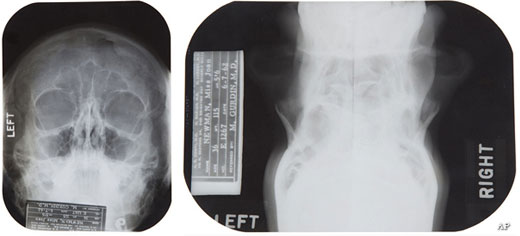

A las reveladoras notas escritas por el médico Michael Gurdin, supuestamente encargado de llevar a cabo la operación quirúrgica en 1950, se suman varias pruebas de rayos X realizadas el 7 de junio de 1962, dos meses antes del fallecimiento de la artista, en las que se pueden apreciar desde diferentes ángulos los huesos faciales de Marilyn, sus conductos nasales y su paladar.

Radiografías de Marilyn Monroe, bajo el nombre de Marilyn DiMaggio, sacadas por un joven médico en 1954.